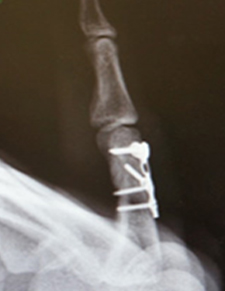

Beşinci metakarpalın boynundaki kırık, kliniğimizde çok yaygındır. Volar plaka fiksasyonu, erken mobilizasyona izin verdiği ve ekstansör tendon yapışmasını önlediği ve cerrahi yara izi yerleşiminin avuç içinde olması nedeniyle tercih ettiğimiz tedavi yöntemidir.

Uygun implantlarla sabitlenen kırıklar erken el tedavisine izin verecektir. Komplikasyonlar arasında hareketi engelleyen uzun vidalar veya teller, kırık parçalarının kötü hizalanması, tendonların sıkışmasına ve hareketi engellemesine neden olan çok büyük implantlar ve cilt ve dokuların uygunsuz yönetimi nedeniyle oluşan ciddi enfeksiyonlar yer alır. Bunlar potansiyel olarak iyileşmeyi ve işe veya spor aktivitelerine erken dönüşü yavaşlatabilir.